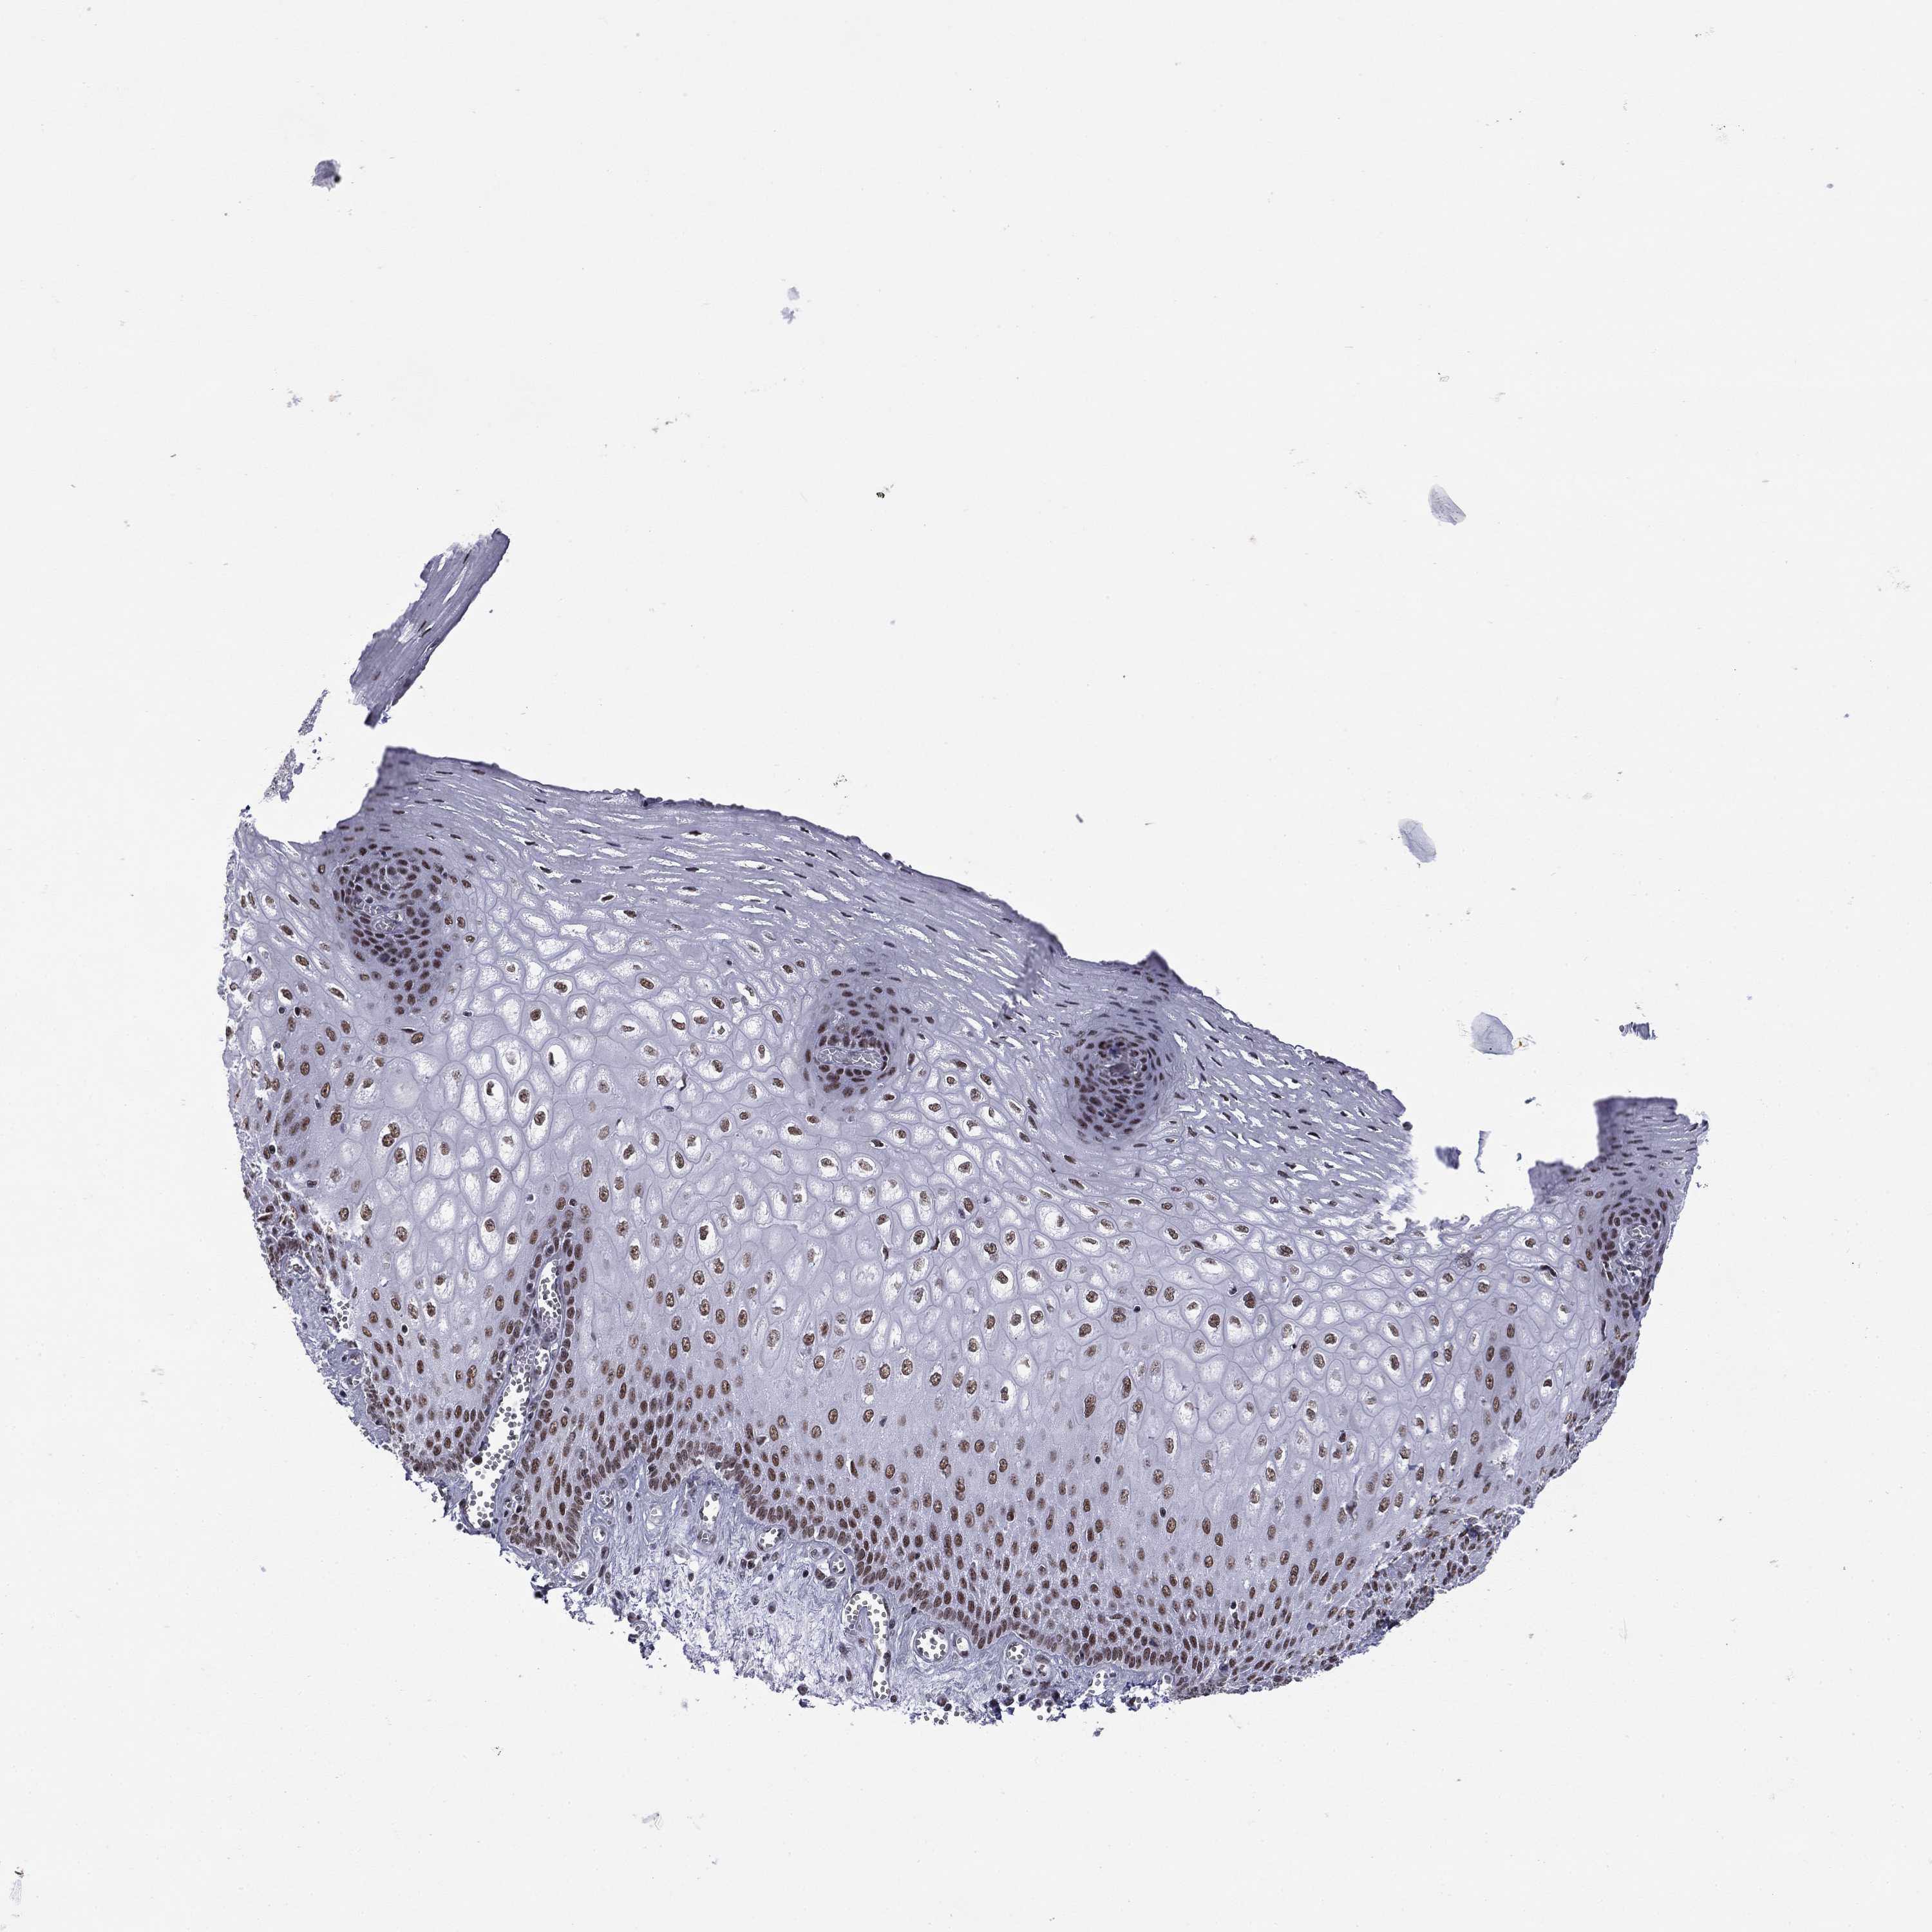

TISSUE PRIMARY DATA ESOPHAGUS Show tissue menu

Esophagus

ESOPHAGUS - Expression summary

Protein expression

Esophagusi

On the top, protein expression in current human tissue, based on all annotated cell types, is reported with the units not detected (n), low (l), medium (m) and high (h). Underneath, protein expression in each annotated cell type are reported using the same units.

Protein expression data is based on knowledge-based annotation. For genes where more than one antibody has been used, a collective score is set.

ESOPHAGUS - Antibody stainingi

Antibody staining in the annotated cell types in the current human tissue is reported as not detected, low, medium, or high, based on conventional immunohistochemistry profiling in selected tissues. This score is based on the combination of the staining intensity and fraction of stained cells.

Each image is clickable and will lead to virtual microscopy that enables deeper exploration of all samples and also displays staining intensity scores, fraction scores and subcellular localization as well as patient and tissue information for each sample.

Antibody HPA073889Antibody CAB009590

Squamous epithelial cells MediumMedium